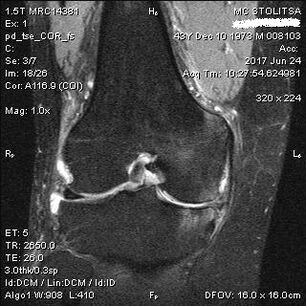

O diagnóstico da artrose da articulação do joelho ocorre no consultório de um reumatologista ou ortopedista. O médico examina a articulação afetada, apalpa, ouve reclamações e faz perguntas adicionais. Realiza diversos testes - por exemplo, pedindo ao paciente que dobre a perna ou dê alguns passos. Então, caso seja necessário esclarecer o estágio da doença ou a natureza das alterações patológicas, ele o encaminhará para estudos adicionais. Por exemplo, para tomografia computadorizada ou radiografia.